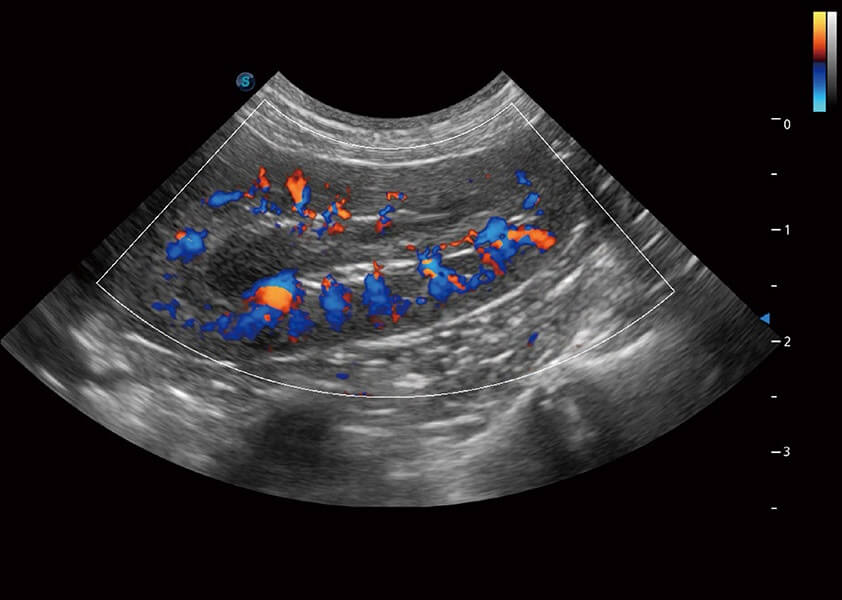

SR Flow 高分辨率血流成像

能够清晰显示细小、低速血流图像,获取传统彩色多普勒技术难以得到的细节和信息。

Micro F 显微血流成像

通过创新的Matrix E自适应滤波器和超长时间域算法,极大提升超低速微细血流的检出能力,同时更精准地滤除软组织和噪声信号,为兽用医生提供以往无法通过常规血流获得的疾病诊断信息。

优异的基础图像

(犬)肾脏血流